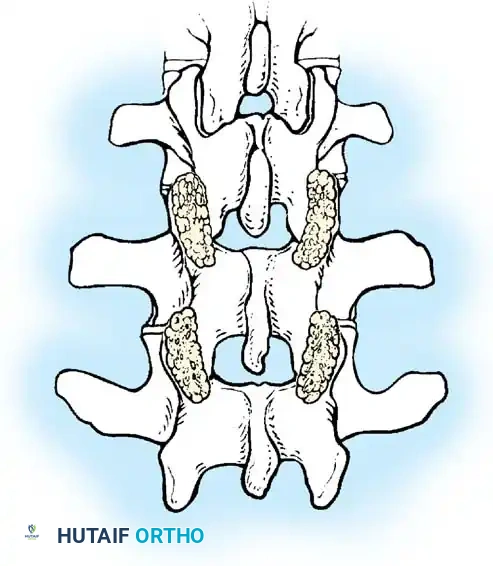

The Moe Technique (Lumbar Spine)

In the lumbar spine, the facet joints are oriented in a more sagittal plane, necessitating a modified approach.

Fig. 38-27: The Moe technique adapted for lumbar facet fusion, addressing the sagittal orientation of the joints.

- Utilize a small osteotome or a needle-nose rongeur to resect the adjoining joint surfaces.

- This creates a distinct rectangular defect within the sagittally oriented joint space.

- Pack this defect forcefully with cancellous bone graft.

- Proceed to decorticate the entire exposed posterior elements (laminae and transverse processes) using Cobb gouges, always directing force away from the spinal canal.